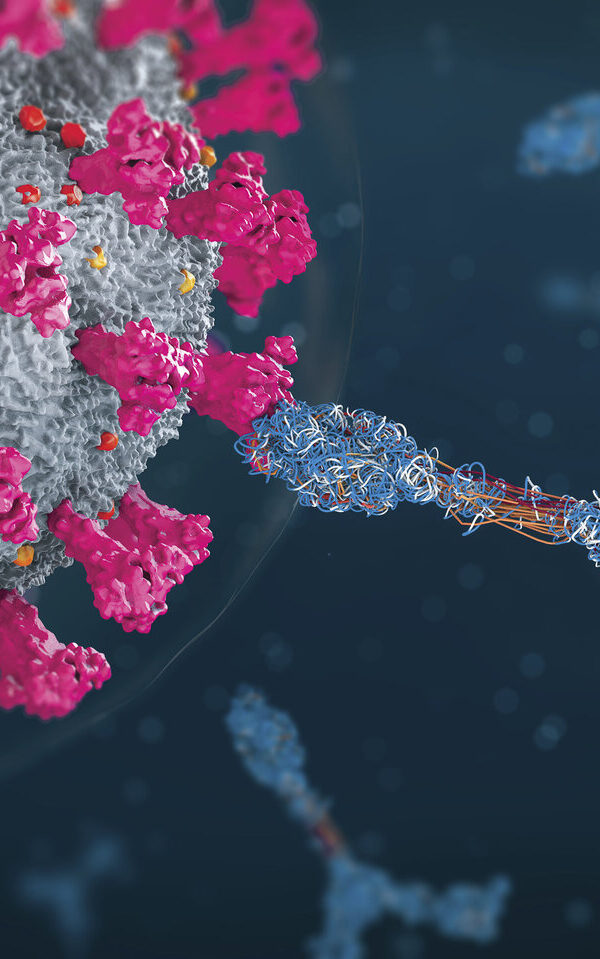

آن شرکتها اشاره کردند که نتایج نه براساس زمان تولدم بلکه براساس میزان پیری سلولها و اندامهایم خواهند بود. هزینه هر آزمایش چند صد دلار بود. شرکتهایی که این آزمایش را انجام میدهند اشاره کردند میتوانند به متقاضیان کمک کنند تا در مورد سلامت خود بهتر تصمیم گیری نمایند. آن شرکتها هم چنین مکملهای بهداشتی میفروشند که به گفته کارکنانشان میتوانند به مبارزه با پیری یا کُند کردن روند آن کمک کنند. این آزمایشها مبتنی بر متیلاسیون DNA هستند.